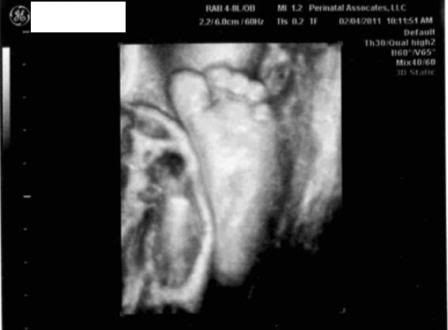

This was taken this morning - it looks so big!

As of last week's u/s, he was measuring perfectly at 4 lbs, 1 oz. Our big surprise this morning was that he already has hair! Usually they can start to detect a small amount of hair (if the baby has any) around 36 weeks - at nearly 34 weeks he already has a lot! I guess I should go invest in some baby hair products.